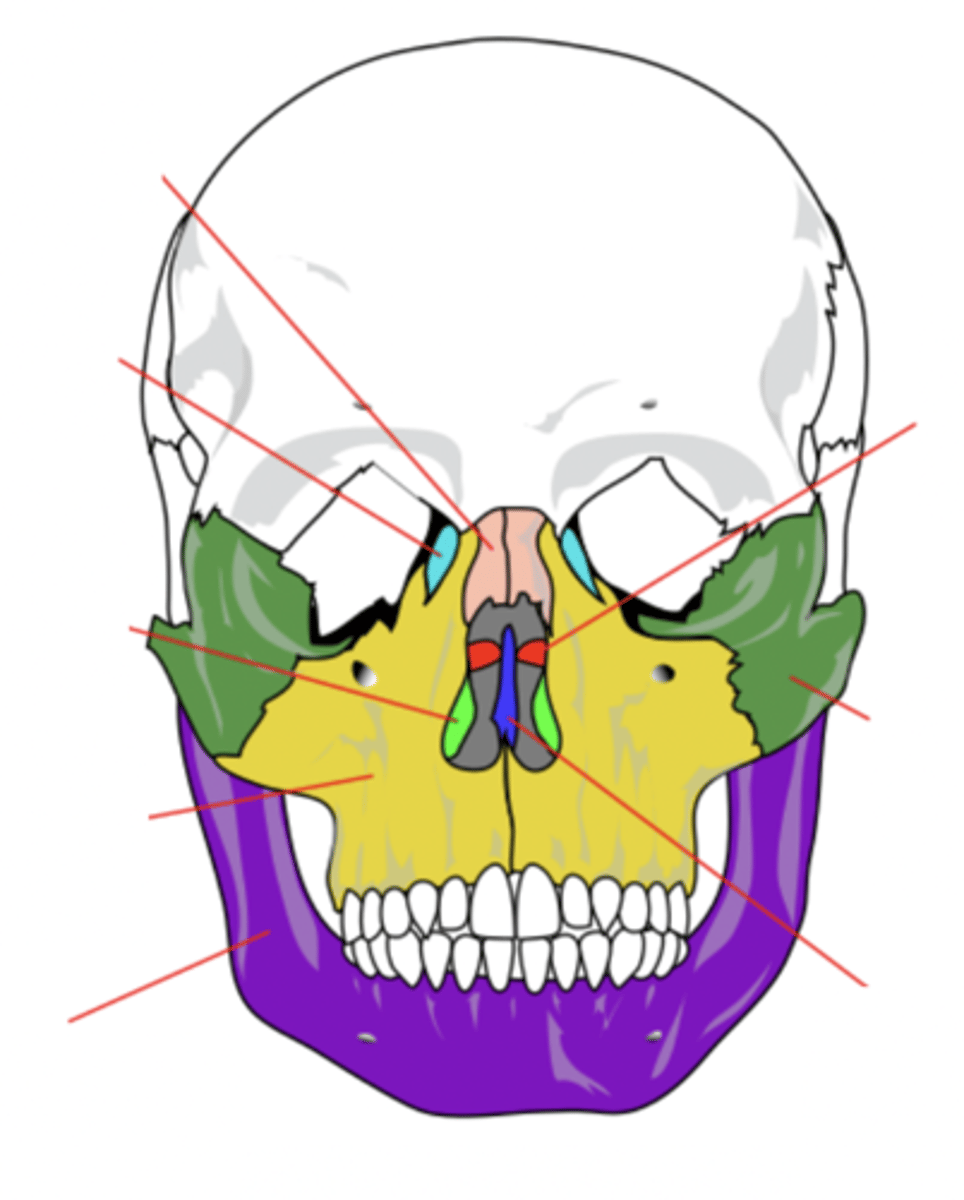

Facial Bones (14)

- Maxilla (2)

- Mandible

- Lacrimal (2)

- Palatine (2)

- Inferior conchae (2)

- Vomer

- Nasal (2)

- Zygomatic (2)

(Many Mammals Like Playing In Very Nice Zoos)

Maxilla Bone (2)

Upper jaw bone (yellow)

Mandible Bone

Lower jaw bone (purple)

Lacrimal Bone (2)

Small fragile bone making up part of the front inner walls of each eye socket and providing room for the passage of the lacrimal ducts (light blue)

Palatine Bone (2)

Bone that forms the hard palate and parts of the nose and orbits (red)

Inferior Conchae Bone (2)

The thin, scroll-like bones that form part of the interior of the nose (light green)

Vomer Bone

Bone that forms the inferior portion of the nasal septum (blue)

Nasal Bone (2)

Bone that forms the bridge of the nose (pink)

Zygomatic Bone (2)

Cheek bone (green)